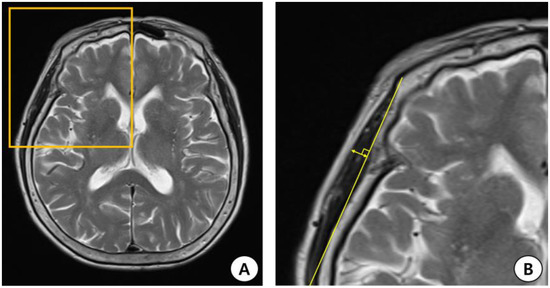

In this study, two researchers (department of rehabilitation medicine physicians) manually measured TMT using T2-weighted MR images obtained at the time of admission for acute stroke. In the picture archiving and communication system (PACS), the slice thickness was reconstructed to 5 mm. TMT measurements were performed at the orbital roof level in the axial view of the brain MRI. In addition, we placed an axial image parallel to the anterior commissure–posterior commissure line. Furthermore, considering the anteroposterior orientation, the Sylvian fissure was defined as a reference point [15,16,17]. TMT was measured perpendicular to the long axis of the bilateral temporal muscles using the PACS tool (Figure 1). We summed the measured TMT on both sides and divided it by 2 to calculate the average value, which was used for statistical analysis.

Figure 1.

Process of measuring temporal muscle thickness (TMT) on the brain magnetic resonance image (MRI). (A) Axial T2-weighted MRI at the orbital roof level. (B) The Sylvian fissure is defined as a reference point in the anterior–posterior orientation. TMT was measured perpendicular to the long axis of the temporal muscle.